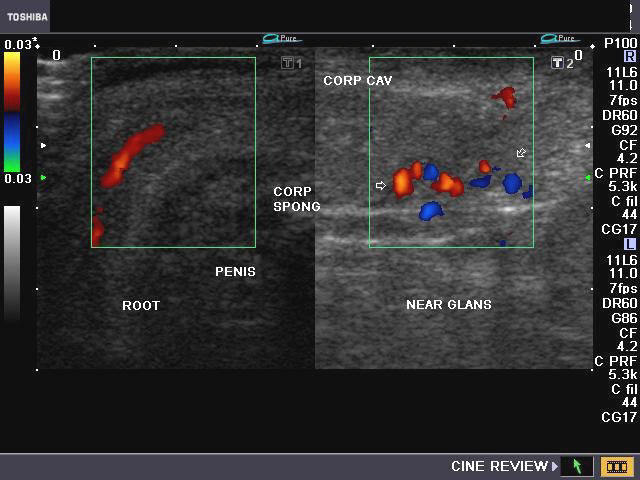

Penile AVM (arterio-venous malformation)/ AVM in the glans of penis

Ultrasound and Doppler images of vascular malformation of the glans penis

This male patient aged 50 yrs. presented with a bout of severe hemorrhage from the penile urethra during coitus for the past 2 days. Sonography and Color as well as Power Doppler imaging of the penis was done. Ultrasound/ Doppler flow images show marked vascularity along the glans of penis. Spectral Doppler waveforms show presence of both arterial and venous flow patterns in the vessels in and around the glans penis. These ultrasound, Power Doppler and Color Doppler images of the penis suggest arterio-venous malformation (AVM) in the glans penis. Trauma during coitus would have precipitated this episode of hemorrhage. The other differential diagnosis would be hemangioma of the glans penis.        (CORP SPONG= corpus spongiosum; CORP AV= corpus cavernosus; Dorsum= dorsal part of the penis). AVM and hemangioma of the glans penis are extremely and hardly any cases are reported in medical literature.